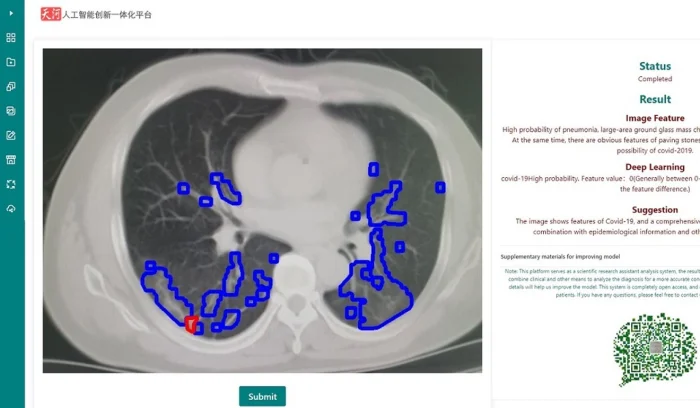

Пока мы с вами листаем ленты новостей, Национальный суперкомпьютерный центр в Тяньцзине занят делом: его система искусственного интеллекта пролистывает сотни снимков компьютерной томографии грудной клетки. На один такой снимок у машины уходит всего 10 секунд. Это не просто скорость — это попытка заглянуть в легкие пациента быстрее, чем вирус успеет нанести непоправимый урон.

Но давайте честно: кому нужна скорость, если она ошибается? Разработчики обещают точность выше 80% и уверяют, что этот показатель растет с каждым днем. ИИ не просто ставит галочку «да» или «нет». Он выдает оценку вероятности заражения от 0 до 10, где ноль — это красный сигнал тревоги. Мало того, система еще и подсказывает врачу, что делать дальше, опираясь на опыт коллег, которые уже прошли этот ад с коронавирусом.

Сейчас этот цифровой помощник уже трудится в более чем 30 больницах, включая Ухань. Сравните сами: опытному врачу нужно около 15 минут, чтобы проанализировать 300 снимков. ИИ справляется за 10 секунд. И что особенно круто — доступ к системе можно получить даже с мобильного телефона. Врачи в «красной зоне» могут сверяться с диагнозом, не отходя от пациента.